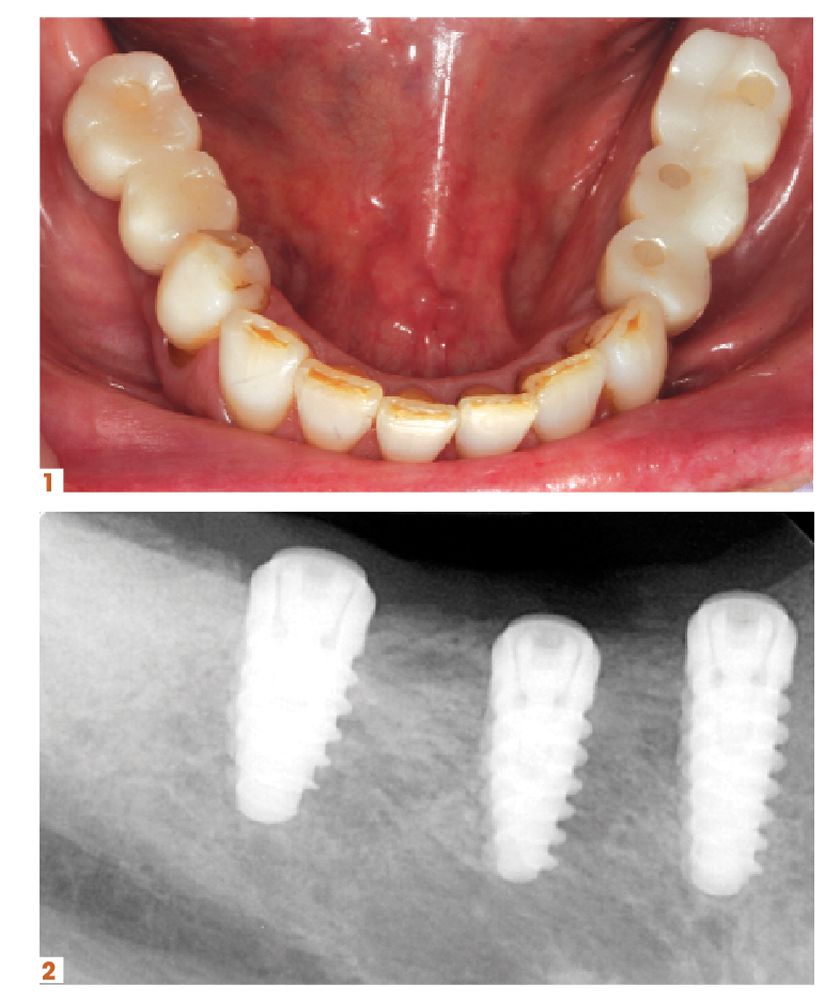

Another area of growth for practices can come from providing more implant services.

“Twenty-two years into my career, I didn’t realize how big of a game changer implant placement would be for my practice. Now that we can tell patients that we can handle it here in the practice, most patients are eager to move forward with treatment,” says John R. Nosti, DMD. “It’s, ‘Oh, you can do this now? That’s great!’

“So being able to offer that service to my patients, who trust me and know that I’m capable of providing them the care or I wouldn’t offer it to them, has been great for them as well as my practice. It’s convinced a lot of patients who’ve been on the fence, even though they wanted the implant, into accepting treatment. And then there’s new patients I’m meeting who have been to my website or seen the marketing pieces we’ve put out. They’ve seen the smiles we create and the testimonials, and they come to the practice because it’s all done in my office.”

There are a few products, and courses, in particular that Dr Nosti counts on to help with his growth.

“I strongly recommend that anyone who’s interested in placing implants take the Misch-Resnik Implant Institute continuum. Just in the first session alone, you learn enough about extracting and grafting to bring that back to your practice and add it to the services you offer,” he says. “Being able to perform predictable bone grafting procedures for your patients can add enough revenue to your practice to pay for the entire continuum. And that’s before implant placement even enters the picture.”

He adds, “Doctors really owe it to themselves to look into implants and have that be a part of their practice. Their patients will be able to chew food easier, smile with more confidence, and enjoy all of the life improvements that implants bring. And that’s amazing because, don’t we all want to better our patients’ lives?”